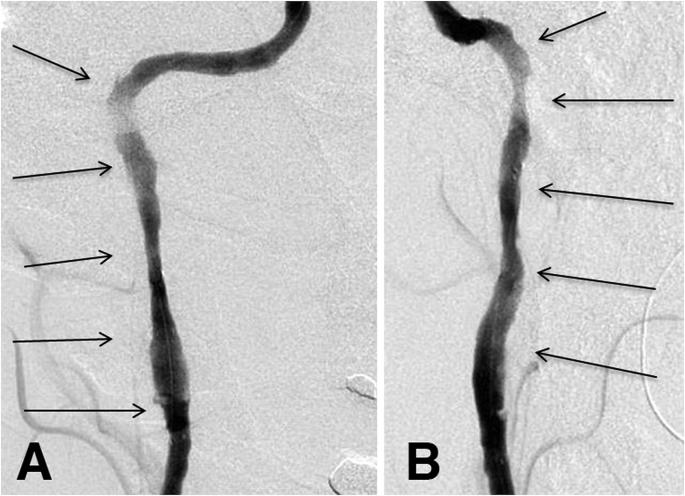

A patient whose initial neuro-ophthalmic manifestation was Horner syndrome, but who evolved over 14 days to display transient monocular vision loss, ipsilateral ocular ischemic syndrome, and episodic contralateral hemiparesis. Digital subtraction angiography demonstrated progressive ipsilateral carotid occlusion with lack of collateral flow. The patient underwent stenting with rapid reversal of transient monocular visual loss and hemiparesis. Follow-up examination several months later confirmed complete resolution of all clinical abnormalities.

一名患者最初的神经眼科表现为霍纳综合征,但在14天内病情进展,出现短暂性单眼视力丧失、同侧眼部缺血综合征和发作性对侧偏瘫。数字减影血管造影显示同侧颈动脉逐渐闭塞且无侧支血流。该患者接受了支架置入术,短暂性单眼视力丧失和偏瘫迅速逆转。数月后的随访检查证实所有临床异常均已完全消失。